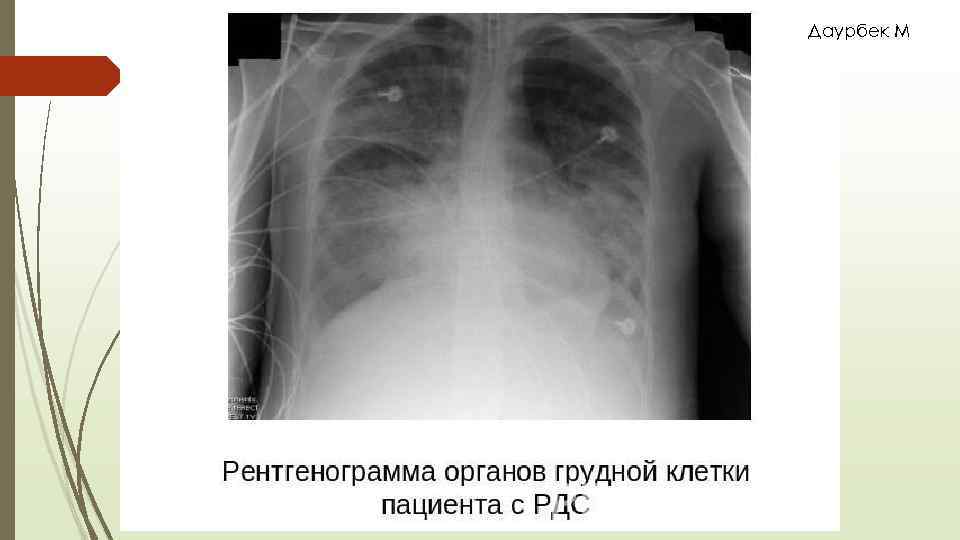

Даурбек М 1990 жылы Фишер мен Фоекс РДС диагностикалық критерийіне келесілерді ұсынды: Интерстициальды өкпе ісінуі ( матовое стекло, снежная буря)

Даурбек М